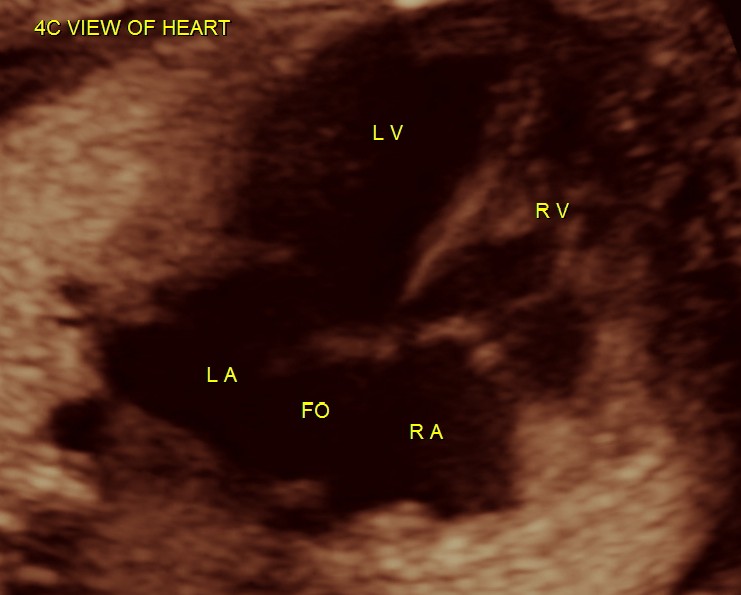

4 chamber view is given below .

Under normal circumstances the chamber in front of descending aorta is left atrium ; and the aorta arises from the left ventricle which has no trabeculations ; the pumonary artery which divides into the two branches arises from the anterior right ventricle and crosses over the aorta .

here we can see the pulmonary artery with its two branches arising from the lower (left) ventricle .and the aorta arising from the anterior (right ) ventricle.